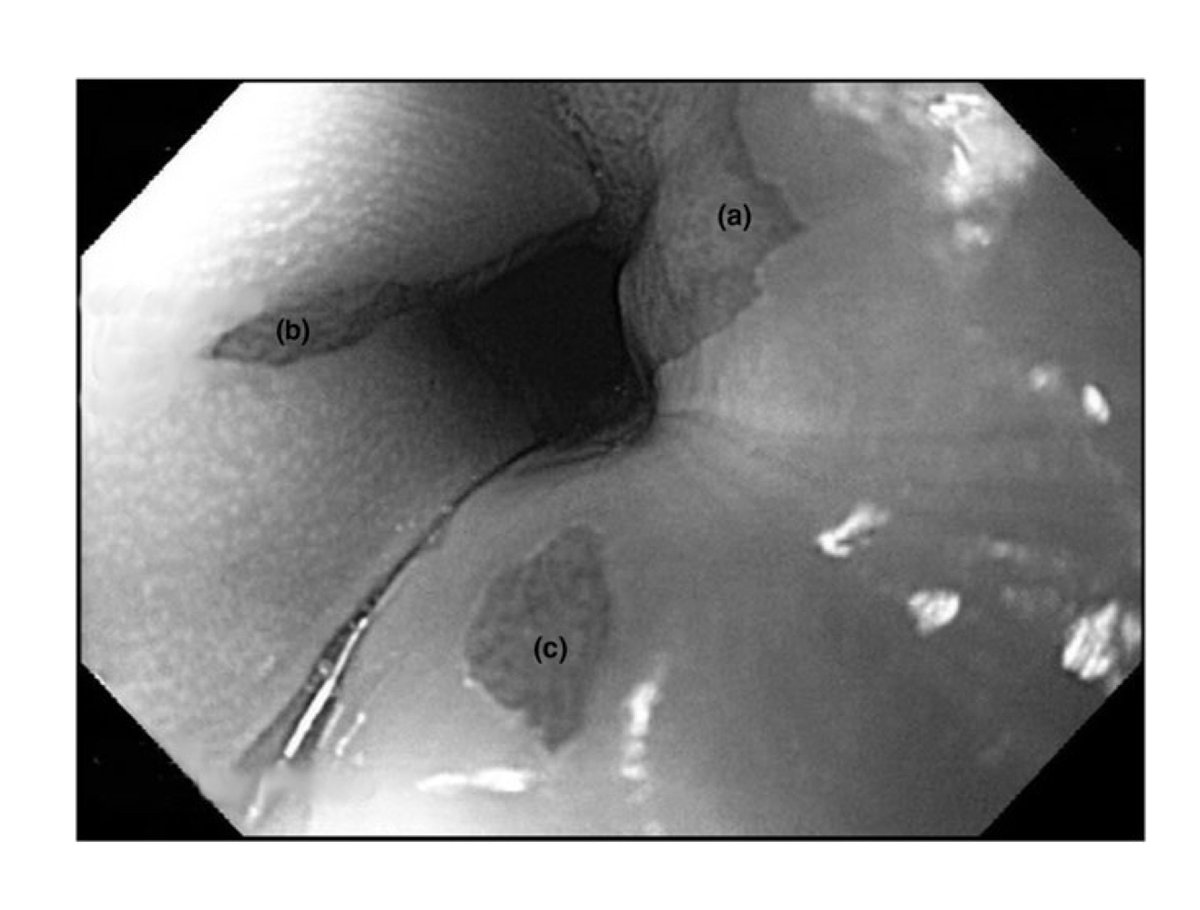

#GUTImage from the paper by Bang et al on "Endoscopic or surgical gastroenterostomy for malignant gastric outlet obstruction: a randomised trial" via https://t.co/Jyp5VBfwgz #Endoscopy #GastricOutletObstruction